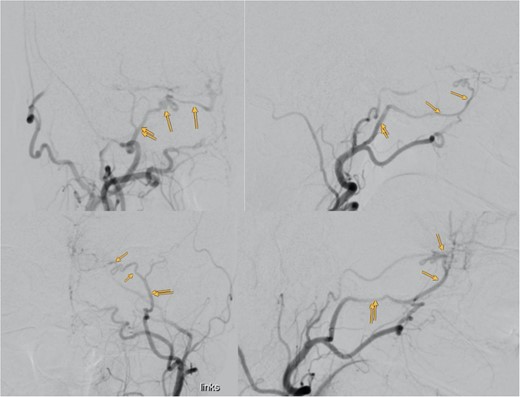

Despite normal blood hormonal status except for low cortisone levels, the patient’s confusion improved upon initiation of physiological and pharmacological cortisone replacement therapy. Digital subtraction angiography revealed that the meningioma was predominantly supplied by bilateral sphenopalatine arteries and bilateral anterior cerebral arteries, with anastomosis through the COF (Fig. 3).

Showing the digital subtraction angiography of the left external carotid artery in four perspectives: posteroanterior view (upper left), lateral view (upper right), posteroanterior view (lower left), and lateral view (lower right). Additionally, the figure shows the middle meningeal artery and the anastomosis, which are marked.

Preoperative embolization of the maxillary and sphenopalatine artery branches bilaterally via ECAs was performed to reduce blood loss risks. However, to avoid the risk of Gelfoam reflux emboli leading to blindness, only the nearest terminal branches to the meningioma were partially embolized.

Our case’s angiography revealed the meningioma’s vascular supply from bilateral sphenopalatine arteries and bilateral anterior cerebral arteries, with anastomosis through COF (Fig. 3). Catheterizing the ECA with such anastomosis poses challenges, especially near the ophthalmic artery. Caution during procedures, proper catheter positioning, and gentle injection techniques are crucial for safe embolization [4].